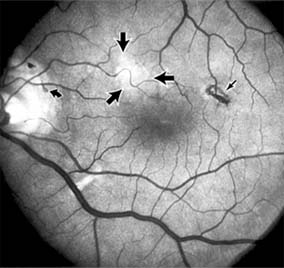

Figure 10-3

Figure 10-3: Fluorescein angiogram of central serous chorioretinopathy shows active disease with both a retinal pigment epithelial detachment (small arrows) and a sensory retinal detachment (large arrows). Two foci of inactive disease (open arrows) are also present.

The diagnosis is made by slitlamp examination of the fundus; the presence of serous detachment of the sensory retina in the absence of ocular inflammation, subretinal neovascularization, an optic pit, or a choroidal tumor is diagnostic. The retinal pigment epithelial lesion appears as a small, round or oval, yellowish-gray spot that is variable in size and may be difficult to detect without the aid of fluorescein angiography. Fluorescein dye leaking from the choriocapillaris may accumulate below the pigment epithelium or sensory retina, resulting in a variety of patterns including the well-recognized smokestack configuration.

Central serous chorioretinopathy is characterized by serous detachment of the sensory retina as a consequence of focal leakage of fluid from the choriocapillaris through a defect in the retinal pigment epithelium (Figures 10-2 and 10-3). This disease typically affects young to middle-aged men and may be related to life stress events. Most patients present with the sudden onset of blurred vision, micropsia, metamorphopsia, and central scotoma. Visual acuity is often only moderately decreased and may be improved to near-normal with a small hyperopic correction.